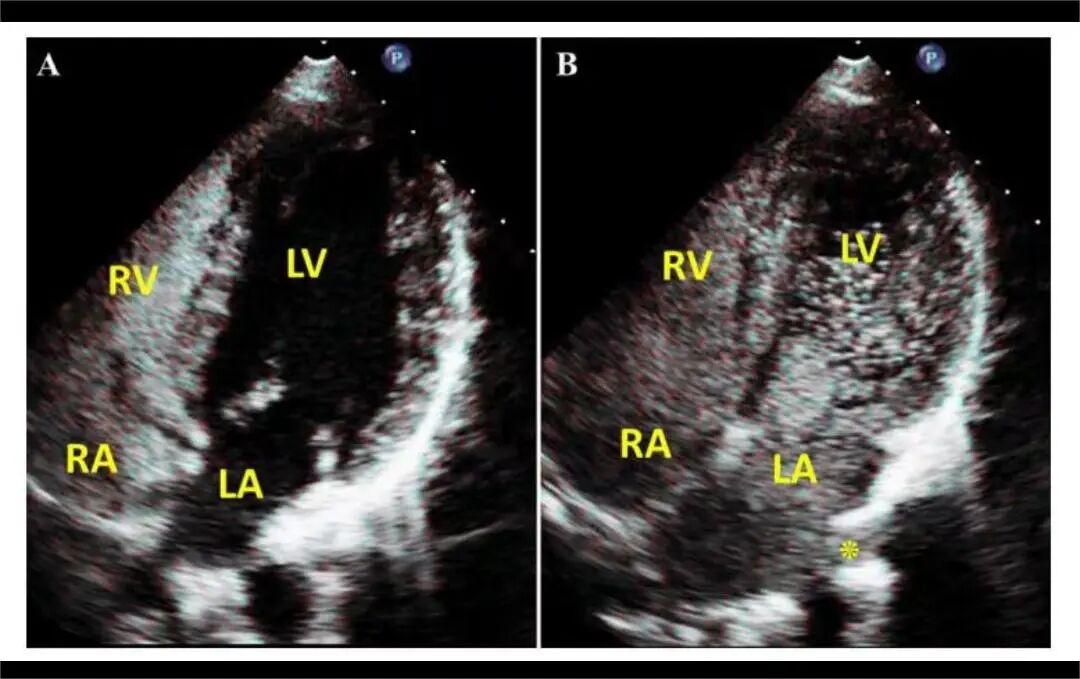

4月2日,贵州航天医院第55次晨读会由我院超声科医师敖春庆作学术交流,她以“中孕期产前超声筛查技术”为题,详细讲解了进修学习的成果,分享了科室实际开展的病例,阐述了未来的工作计划与展望,并结合典型病例图文分析等形式,强调了中孕期产前超声筛查的重要意义。 超声科专家简介 吴艳辉 中共党员,超声科学科带头人、主任,主任医师 临床擅长:从事超声诊断工作约30年,对心血管、小器官超声、超声引导下介入等具有丰富的临床经验。 骆科美 中共党员,超声科副主任医师 临床擅长:从事超声诊断工作33年,对胎儿心脏及颅脑、妇产超声、盆底超声等诊断具有丰富的临床经验。 胡大海 超声科副主任医师 临床擅长:从事超声工作17年,对心血管、外周血管、浅表器官超声诊断等具有丰富的临床经验。 刘 敏 超声科副主任医师 临床擅长:从事超声诊断工作20余年,对妇产科超声、心脏血管超声诊断具有丰富的临床经验。 敖春庆 超声科主治医师 临床擅长:对腹部、泌尿、妇科等超声诊断具有丰富的临床经验。 超声科简介 基本情况 贵州航天医院超声科配备多种超声检查设备(飞利浦彩超(IU-22、IU-Elite、HD11、Q5、Q7),迈瑞超声I9、DC-6、DC-8、GE-E8及床旁机,彩色超声诊断仪等),设有心血管诊室、妇产科诊室、腹部诊室、浅表小器官等检查室。 专科特色 四肢血管超声检查、双胎产前筛查及超声监护、超声造影检查技术、介入超声临床应用、经颅脑实质超声辅助筛查诊断帕金森病、女性性早熟超声诊断、盆底超声检查等。 NT超声检查 超声介入引导 肝脏超声造影 甲状腺造影 颅脑超声帕金森辅助检查 乳腺超声造影 上肢动静脉造瘘超声检查 双胎超声筛查 下肢血管超声检查 右心造影 诊疗范围 科室业务覆盖腹部、泌尿、妇科、产科(常规、NT筛查、III级筛查超声检查及高危妊娠监护)、成人心脏、外周血管、浅表器官(包含甲状腺、乳腺、阴囊、眼睛等)、颅脑(小儿颅脑、成人颅脑)、小儿肺超、造影、盆底、腹直肌、肌骨神经等检查及各种介入引导。 end